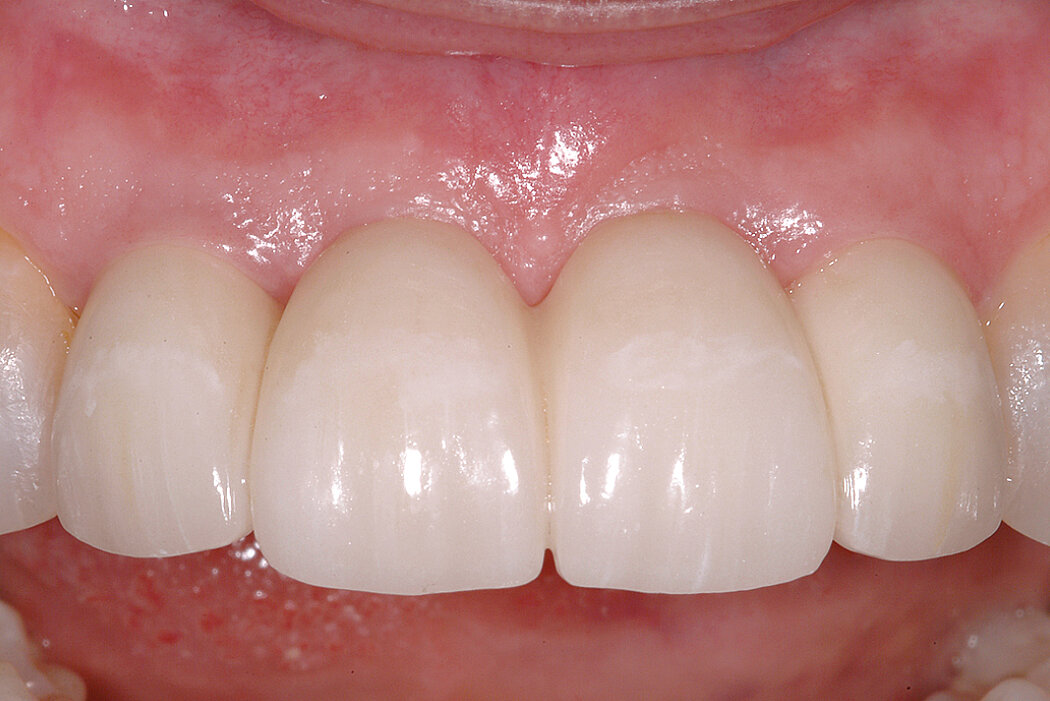

Conclusion

Minimal horizontal bone loss and widening of the keratinized gingiva thanks to Ridge Preservation with Geistlich Bio-Oss® Collagen and Geistlich Bio-Gide® Shape. On the regenerated side 3 months postoperative the red-white esthetics are just as good as on the natural tooth side.